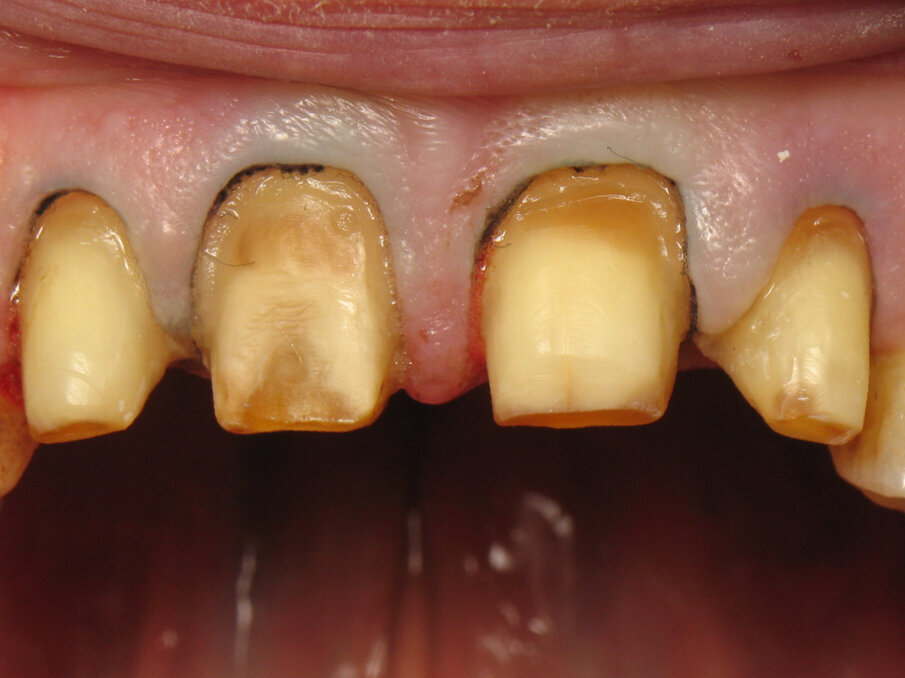

Fig. 11: Initial situation.

Fig. 12: Close-up of the initial situation.

Captured at the same time as Figure 10, Figures 11 and 12 show the initial situation of this patient, who came for a consultation to rehabilitate his maxillary incisors. The diagnosis revealed nocturnal bruxism as the origin of several areas of crown destruction: wear of the incisal edge, abfraction, missing restorations, cracks and a complex coronary fracture. It is easy to understand why the choice of material was zirconia. It is also easy to understand the motivations of this patient to recover his lost smile. This degradation over time is inevitable, but in this patient, it was particularly fast and aggressive. Reversing the course of time was therefore obvious in restoring the dental health of this patient.